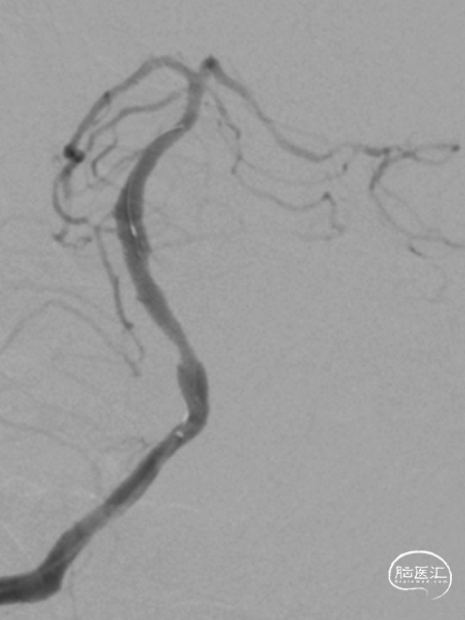

最后影像:椎基底动脉连接处残余狭窄约20%,前向血流改善明显,mTICI3级。远端各血管显影良好,分支较术前增多。

半年后复查造影:支架内无明显再狭窄。椎基底动脉通畅,前向血流mTICI3级。